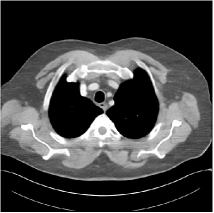

Refer to caption WavResNet [11]Refer to caption WavResNet [11]Refer to caption WavResNet [11]Refer to caption Momentum-Net (SimpleCNN)Refer to caption Momentum-Net (SimpleCNN)Refer to caption Momentum-Net (SimpleCNN)Refer to caption Momentum-Net (SimpleCNN-RSN)Refer to caption Momentum-Net (SimpleCNN-RSN)Refer to caption Momentum-Net (SimpleCNN-RSN)Refer to caption Momentum-Net (Dn-RSN)Refer to caption Momentum-Net (Dn-RSN)Refer to caption Momentum-Net (Dn-RSN)Refer to caption ReferenceRefer to caption ReferenceRefer to caption Reference

Refer to caption Refer to caption Refer to caption Refer to caption Refer to caption Refer to caption Refer to caption Refer to caption Refer to caption Refer to caption Refer to caption Refer to caption Refer to caption Refer to caption Refer to caption

Fig. 3: Three examples (from top to bottom) of the reconstructed testing images using Momentum-Net with SimpleCNN (the second column), with SimpleCNN-RSN (the third column), and with Dn-RSN (the fourth column). The compared WavResNet denoised images are shown in the first column, and the reference images are in the fifth column. See their FBP images in Fig. 4.

Fig. 2 shows that the proposed Momentum-Net with SimpleCNN decreases RMSE dramatically in the first 30 layers, and tends to converge in 50 layers. The Momentum-Net reduces the mean RMSE value by 4.5 HU and gives smaller standard deviations in RMSE, compared to WavResNet, as reported in Table 1. This implies that the proposed Momentum-Net with SimpleCNN can improve both the accuracy and stability of low-dose CT image reconstruction than a state-of-the-art image denoising deep NN, WavResNet. The proposed Momentum-Net with SimpleCNN better removes noise and streak artifacts than WavResNet. It also provides clearer reconstructions of some details; see, in Fig. 3, the boundaries shown in the zoomed region at the top-right corner in the first example, the arrow pointed structures in zoomed areas of the second example, and the arrow pointed tissues in the left zoomed region in the third example.

3.3 Momentum-Nets involving RSN-based training